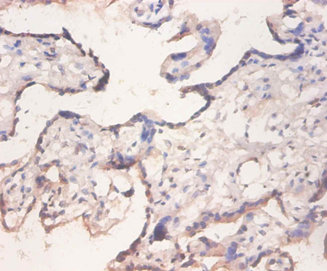

ApplicationELISA, IHC; Recommended dilution: IHC:1:20-1:200